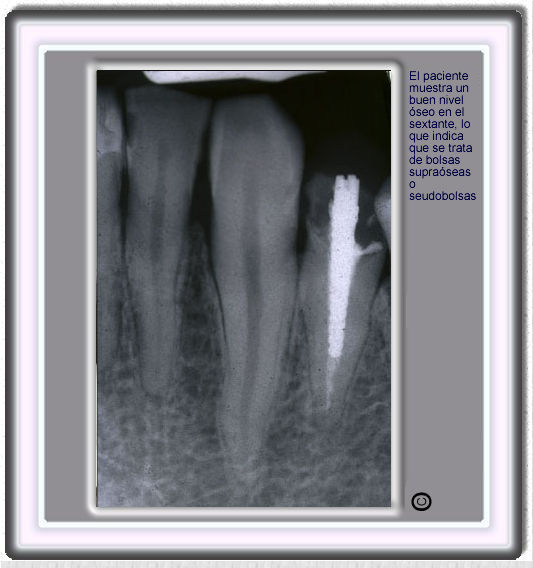

image 89